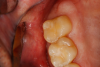

Fig 45. Finished restoration, ready for endodontic entry.

Figure 45

Fig 46. Close-up of polished surface.

Figure 46